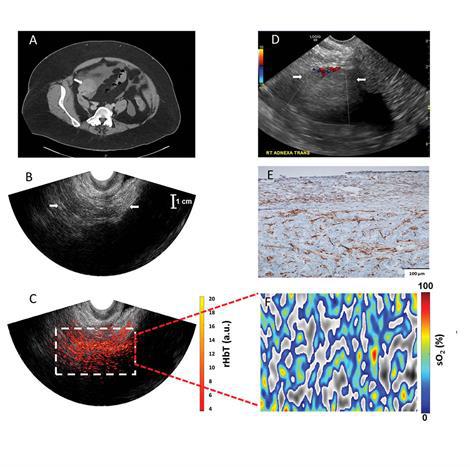

‘Hopeful technology’ could change detection, diagnosis of deadly ovarian cancer

Quing Zhu, professor of biomedical engineering in the School of Engineering & Applied Science and of radiology, and a team of physicians and researchers at Washington University School of Medicine recently conducted a pilot study using co-registered photoacoustic tomography with ultrasound to evaluate ovarian tumors on 16 patients at the School of Medicine and Barnes-Jewish Hospital. Results of the study are published online in Radiology.

"When ovarian cancer is detected at an early, localize